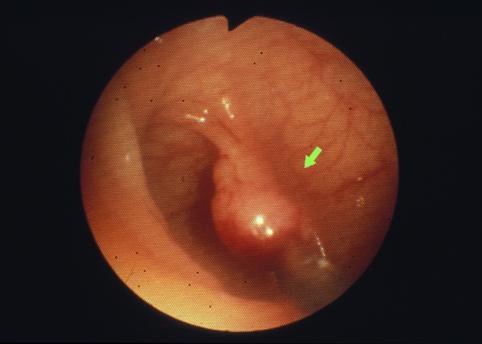

질환(병리주체)의 분류 악성 상피성종양/선암

부위(장기별) 대장/S상

검사방법 내시경

종양의 육안분류 0형(표재형)/IIa형(IIa)

종양의 최대경(밀리미터) 10~14

종양의 심달도 sm